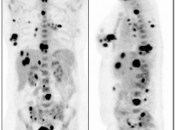

Diffuse Skeletal Uptake:

Intense and diffuse reactive marrow uptake is frequently seen as the result of chemotherapy and/or colony stimulating factors (discussed in detail, here).

If rather diffuse and intense uptake is noted without a history of recent chemotherapy or colony stimulating factors, be suspicious of infiltrating disease such as lymphoma.

Focal Skeletal Uptake:

Focal skeletal uptake warrants extremely close assessment of the co-registered CT images to exclude malignancy. Other etiologies of focal skeletal uptake include fracture, arthropathy, infection and several benign bone lesions.